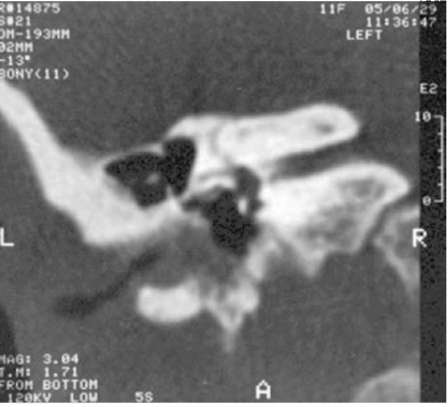

pic 0139

Рис.11-5. КТ, фронтальная проекция. Стеноз окна преддверия (размер 0,7×1,5 мм).

Подробные данные КТ височной кости при оценке структур наружного, среднего и внутреннего уха у детей с врождёнными атрезиями наружного слухового прохода необходимы для оценки технической возможности формирования наружного слухового прохода, перспективности улучшения слуха, оценки степени риска предстоящей операции. Ниже приведены некоторые типичные аномалии (рис. 11-4-11-8).